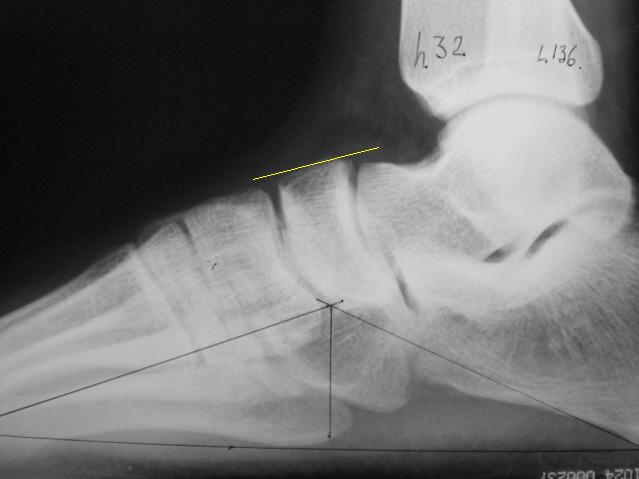

Извиняюсь что несколько не по теме, но вопрос: рост 192, стопа 44 размера

При измерении плоскостопия дичайший разброс от учреждения к учреждению, от 148 до 157 градусов.

Есть расчерченный снимок. Завтра в военкомат. Вопрос, что очень сильно меня волнует: правильно или же неправильно он расчерчен?

vzl2lqh0m0o.jpg